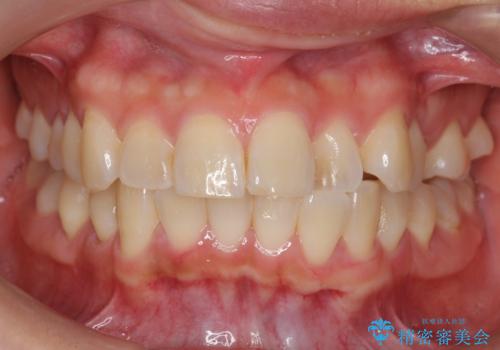

- 前歯の並びを気にして来院。

左上の前歯が内側に入って反対咬合になっていました。

また、左上5番も反対咬合でした。

上のワイヤー矯正を半年ほど行い反対咬合を改善してから、上下インビザライン治療を行いました。

下の前歯を中に入れるためにIPR(歯をわずかに削る処置)を行いました。